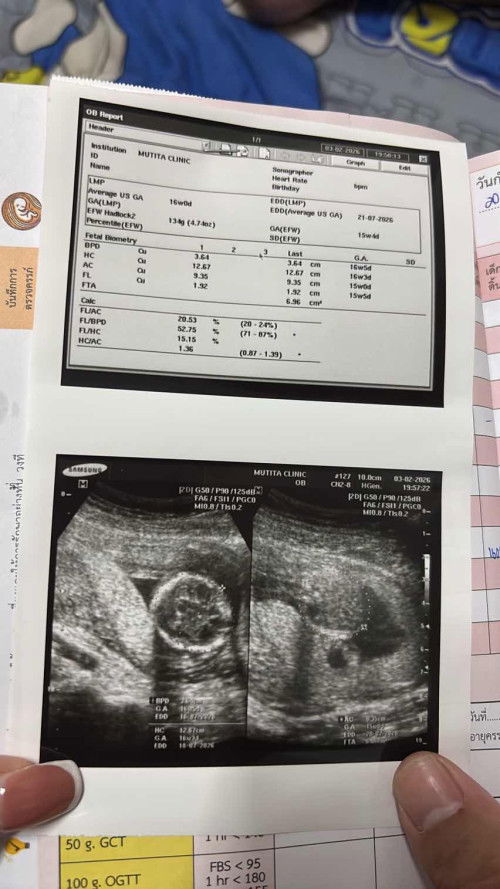

ขอสอบถามแม่ๆหน่อยค่ะ ประจำเดือนล่าสุดที่มาวันแรกของวันที่13เดือนกุมภา ตอนนี้เดือนมีนาหนูตรวจเจอขึ้นสองขีดเมื่อวันที่16 ประจำเดือนตอนนี้ขาดมา5วัน แบบนี้เรียกว่าตั้งครรภ์ไหมค่ะ ตรวจเลือดมาแล้วหมอบอกว่าตั้งครรภ์แต่ไม่รู้กี่สัปดาห์ พอไปซาวด์ยังไม่เจอถุงตั้งครรภ์ แบบนี้เรียกว่าท้องยังอ่อนอยู่ใช่ไหมค่ะ รูปใต้ล่างเลยค่ะ #ขอบคุณสำหรับคอมเม้นล่วงหน้าค่ะ